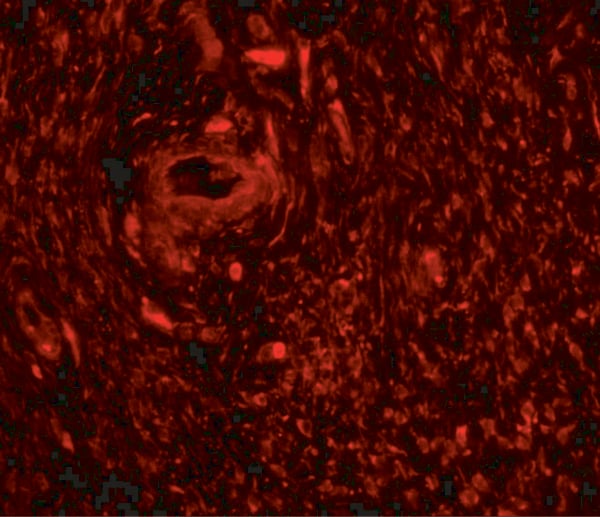

IHC (Immunohiostchemistry)

(The image on the left is immunohistochemistry of paraffin-embedded Human thyroid cancer tissue using AAA240305(ANKRD26 Antibody) at dilution 1/25, on the right is treated with synthetic peptide. (Original magnification: ×200))